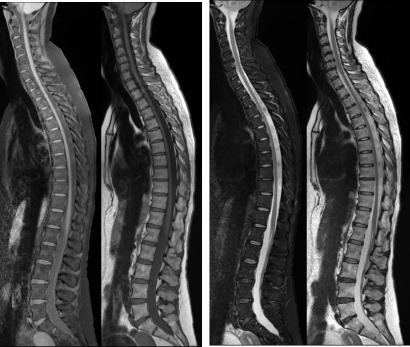

IRM ostéo-articulaire (rachis, articulations des membres supérieurs et inférieurs, tendons, muscles,...)

L’IRM ostéo-articulaire est un examen qui permet l’exploration de l’arthrose, de tendinites, de maladie inflammatoire articulaire, de lésion à la suite d’un traumatisme concernant toutes les articulations du corps, comme le genou, l'épaule, la hanche, le poignet, la main, la cheville et le pied.

L’IRM du rachis permet d’analyser les structures vertébrales et paravertébrales rachidiennes (vertèbre, disque intervertébral, ligaments, muscles) ainsi que les éléments du système nerveux qu’elles contiennent (moelle épinière et racines nerveuses).